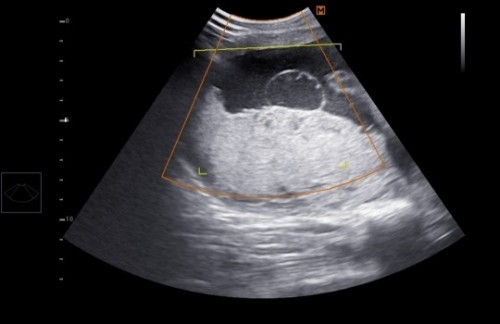

อยากถามแม่ๆท่านอื่น มีใครเคยเป็นก้อนซีสต์ขณะตั้งครรภ์มั้ยคะ ของแม่ตรวจเจอก้อนบริเวณรก ยังไม่มั่นใจว่าใช่ที่รกหรือบริเวณไหน หมอขอเจาะน้ำคร่ำไปตรวจ กำลังรอฟังผล อยากมาสอบถามมีแม่ๆคนไหนมีประสบการณ์แบบนี้มั้ยคะ อันตรายกับลูกมั้ย#ขอคำแนะนำหน่อยค่ะ